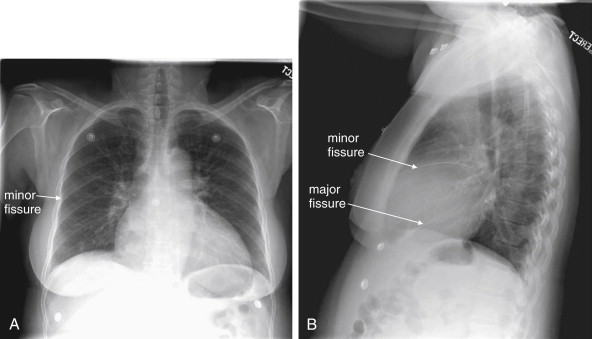

Frontal (Posterior–Anterior or Anterior–Posterior) Upright Chest X-ray View

The normal frontal upright chest x-ray (Figure 5-15 ) has the following features:

The airway is midline.

•

-

The cardiac silhouette occupies less than half of the transverse diameter of the thoracic cavity. The cardiac silhouette is crisp, with no adjacent pleural fluid or parenchymal opacities to disrupt the normal silhouette. The mediastinal width is less than 8 cm, and the aortic knob is well defined. The normal appearance of the aorta is described in detail in Chapters 6 and 7Chapter 6Chapter 7.

The lung fields are clear, without opacities to suggest pleural effusion, parenchymal disease such as infectious infiltrate, or mass lesion. Lung vascular markings are visible to the periphery, without evidence of pneumothorax. Lung markings are less prominent in the lung apices because gravity diverts blood flow to the lung bases.

Figure 5-15.

The normal frontal chest x-ray.

Normal features of the posterior–anterior upright chest x-ray are demonstrated.